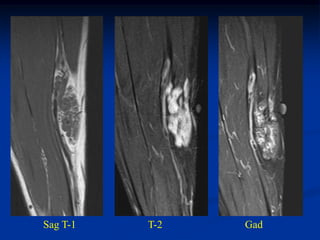

Case #297.1                    Hemangioma forearm

Cor T-1                          Gad

18 year old female with forearm mass for years

Axial T-1

Axial Gad

Case #297.2     Hemangioma forearm

46 yr male with

tender soft mass

forearm for years

Cor T-1   T-2   Gad

Sag T-1   T-2   Gad

Axial T-1         T-2

Gad

Case #297.2 Hemangioma forearm 46 yr male with tender soft mass forearm for years

• 310.

• 311.

• 312.

Axial T-1 T-2 Gad